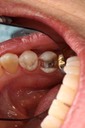

Frank Fukuda #19 pre-op

Frank Fukuda #19 lingual pre-op